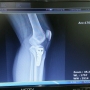

오토바이사고 양쪽어깨 슬랩병변

후유장애진단관련

외상성 뇌출혈 및 척추압박골절 문의